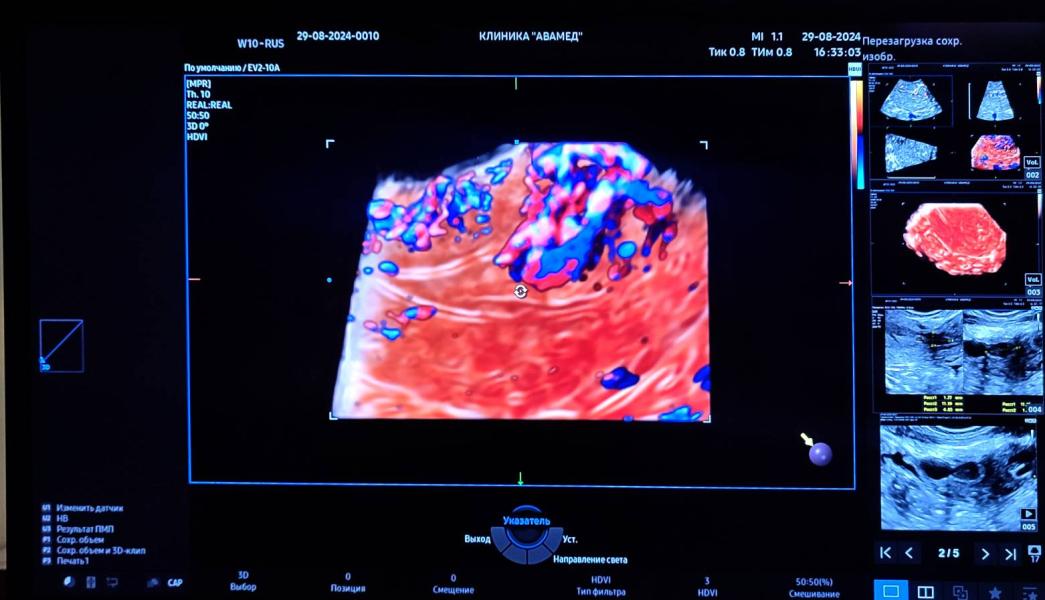

Пациентка после фарм аборта в сроке 8 недель беременности по поводу анэмбрионии ( отсутствие эмбриона в плодном яйце).

В полости матки остатки плодных оболочек, с последующим образованием плацентарного полипа, который питается сосудистой ножкой. В анамнезе одна операция кесарево сечения: в области рубца отмечается дефект передней стенки перешейка матки. В данном случае нужно провести гистероскопию с последующей метропластикой. Беременность с данным дефектом может привести к разрыву матки по ...